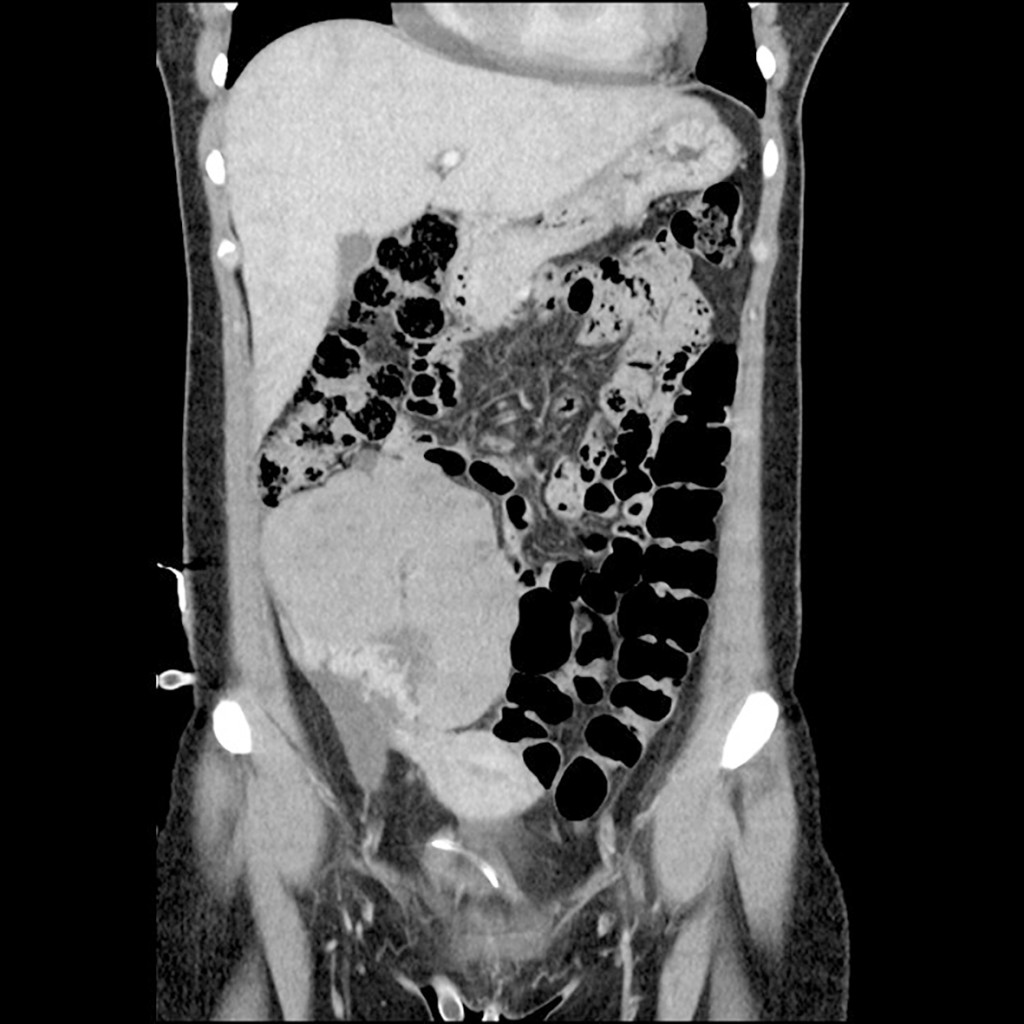

Further diagnostic imaging was performed, including CT thorax, abdomen and pelvis. This verified the echocardiographic finding of an expansive process in the right side of the heart with pericardial effusion. An additional large expansive process measuring 11 x 8 cm was found in the right side of the abdomen, with varying density and contrast enhancement, calcifications and abundant vascularisation. The pouch of Douglas was also shown to contain free fluid and masses with minor contrast enhancement (Fig. 2).

Figure 2 CT abdomen in the frontal plane at the time of diagnosis. A CT scan of the patient after hospitalisation revealed a…

Figure 2 CT abdomen in the frontal plane at the time of diagnosis. A CT scan of the patient after hospitalisation revealed a large mass of 11 x 8 cm in diameter in the lower right quadrant of the abdomen. The mass was of varying density and contrast enhancement, and showed calcifications and abundant vascularisation.